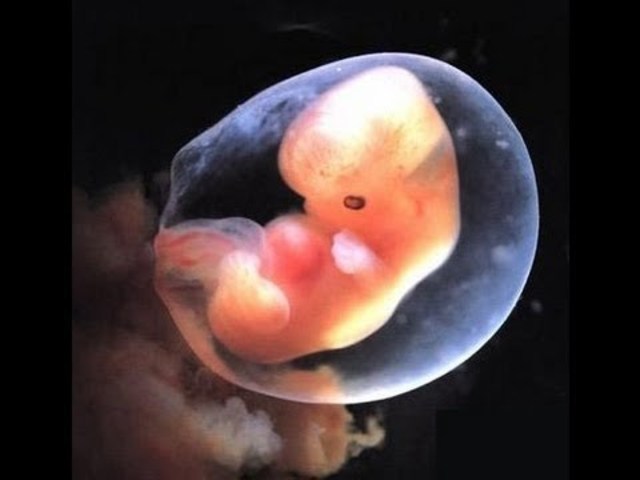

• First Timester (six through eight weeks)

First Timester (six through eight weeks)

Most vital organs are developed, the eyelids are formed, the leg and arm buds begin to form, the bones and muscles begin to form, and the brain is developing. The mother will experience morning sickness, frequent urination, cravings, breast enlargement, and irritability.